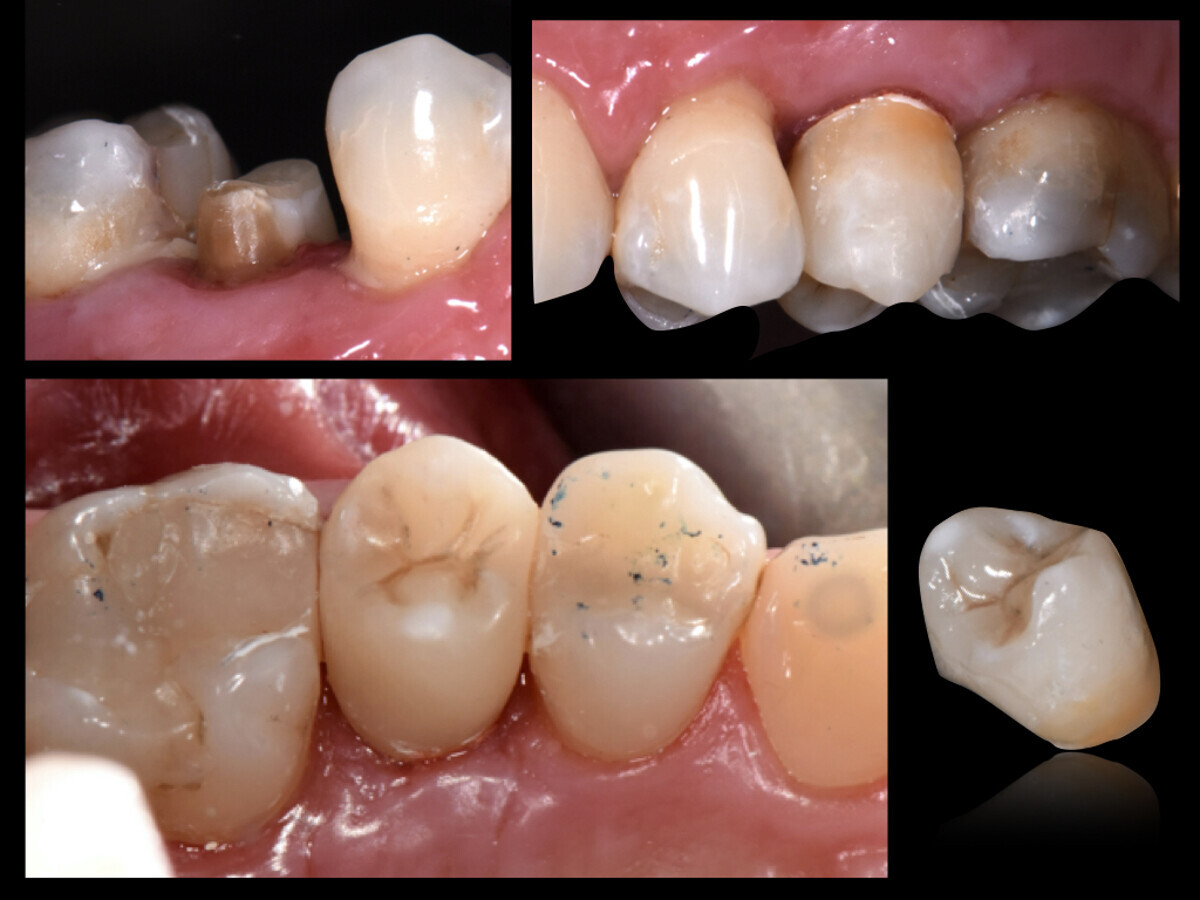

Fig. 3: Fabricación en el mismo consultorio de una prótesis provisional indirecta con un composite autopolimerizable (Structur 3, VOCO) utilizando GrandioSO Inlay System (VOCO).

Secuencia de pasos del tratamiento: primeramente se llevó a cabo el tratamiento endodóntico de urgencia, y una semana después la prolongación quirúrgica de la corona clínica. Diez días más tarde se efectuó la prolongación de los márgenes de la preparación, el tratamiento endodóntico y la inserción de un innovador poste radicular, así como la reconstrucción adhesiva y la preparación del muñón dental (Rebilda Post GT, VOCO). Directamente en el consultorio se fabricó una prótesis provisional indirecta (GrandioSO Inlay System, VOCO) de composite autopolimerizable (Structur 3, VOCO) mediante la técnica de prensado sobre un modelo de silicona del muñón debidamente preparado. Hasta la restauración definitiva con una corona de cerámica pura de disilicato de litio se efectuaron controles clínicos y radiológicos durante cuatro meses.

Fig. 4: Cementación convencional de la prótesis provisional durante cuatro meses (Provicol QM, VOCO), que permanece incorporada hasta la cicatrización completa del tejido. Después, se planifica una restauración definitiva con una corona de disilicato de litio.